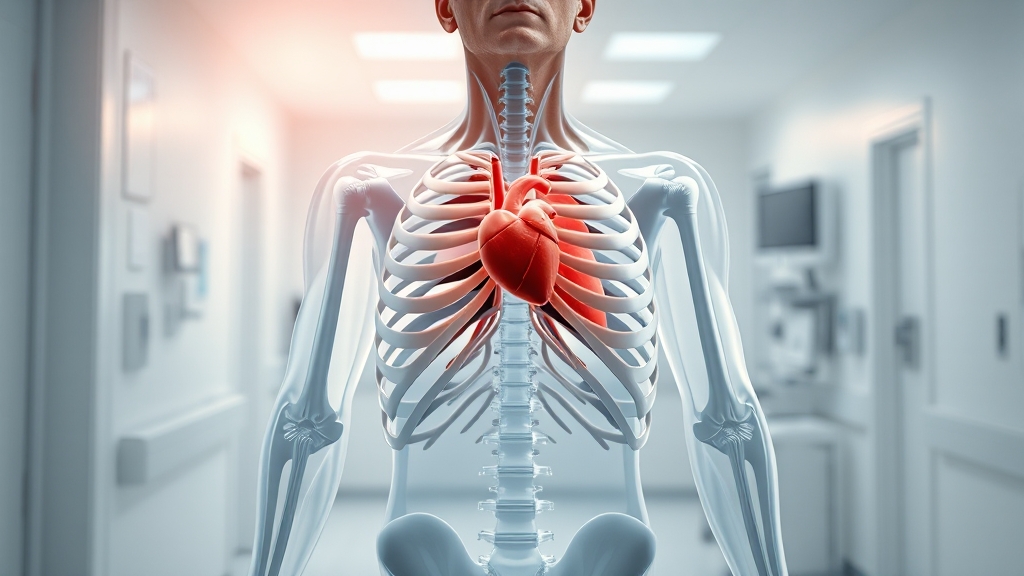

갈비뼈, 왜 중요할까?

갈비뼈는 우리 몸의 가슴을 이루는 뼈로, 총 12쌍이 좌우로 배열되어 있어요. 심장, 폐, 간 등 중요한 장기를 보호하고, 호흡 운동에도 중요한 역할을 담당하고 있답니다. 갈비뼈의 건강은 곧 우리 몸의 건강과 직결된다고 할 수 있어요.

갈비뼈는 단순히 뼈 모양을 유지하는 것 이상의 역할을 해요. 외부 충격으로부터 내부 장기를 보호하고, 폐의 팽창과 수축을 도와 호흡을 가능하게 하는 중요한 뼈대랍니다. 갈비뼈가 손상되면 이러한 기능에 문제가 생길 수 있어요.